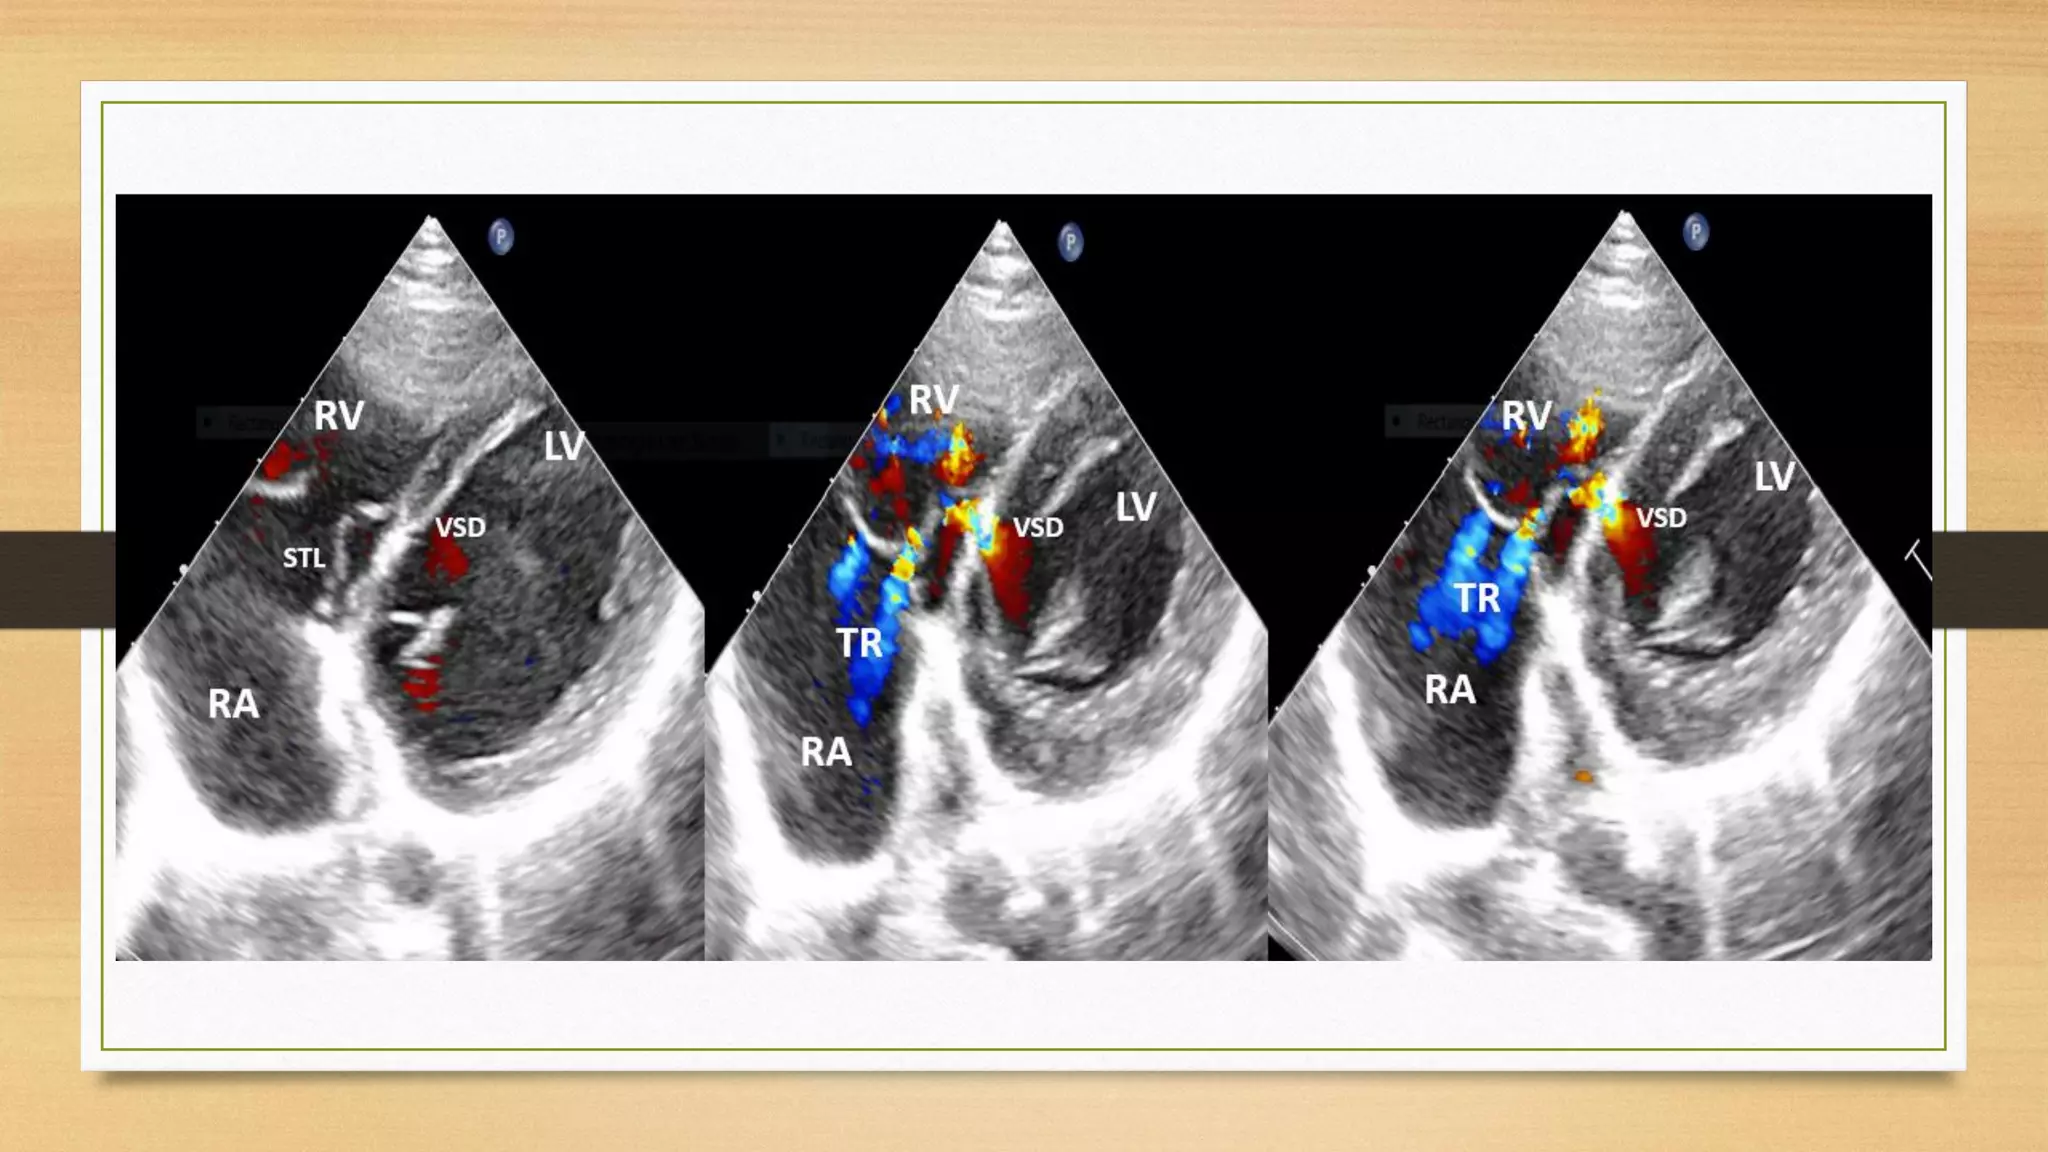

Mid Muscular VSD with TR

The Tricuspid regurgitation with membranous VSD mainly occurred because of

1. short tricuspid valve septa – Dysplastic TV

2. Interminable anterior tricuspid valve septa – Richoceting TR

High velocity jet by impinging on anterior tricuspid leaflet and richoceting as TR.The TR is produced by the VSD jet (

Venturi effect) pushing the tricuspid anterior leaflet forward to open the tricuspid valve orifice and richoceting jet enter

right atrium as TR. In these patients, a moderate paramembranous VSD extended slightly below the septal tricuspid leaflet

with only partial obstruction of the VSD jet. We believe that when this mechanism for TR is found in association with a

moderate VSD, surgical VSD closure is warranted

3. Abnormal attachment point of the chordae tendineae to muscular VSD

4. Irregular adhesion of STL to right ventricular septal defect - Sometimes tricuspid septal aneurysm (which is closing large

VSD) can distort the tricuspid valve and cause tricuspid regurgitation.

If pulmonary arterial pressure is estimated by the tricuspid regurgitation method, the pulmonary artery systolic pressure

would be overestimated. Due to this the differential pressure of the tricuspid valve was not the same as that of the right

ventricle and right atrium, but instead the same as the left ventricle and right atrium.